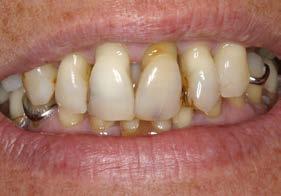

Figuras 2-3. Imágenes intraorales que evidencian pérdida ósea generalizada, extrusión de dientes anteriores y recesiones en todas las piezas presentes.

Se presenta el caso de una mujer de 65 años con diagnóstico de periodontitis severa al inicio del tratamiento. El examen clínico evidenció pérdida

Figura 1. Radiografía panorámica inicial que muestra la enfermedad periodontal avanzada de la paciente, con ausencia de varias piezas dentales y otras de mal pronóstico.

Implantes y propiocepción: la importancia de preservar dientes clave en pacientes con enfermedad periodontal avanzada

ósea vertical generalizada, defectos angulares en sectores posteriores y múltiples ausencias dentarias en ambos maxilares. La inspección intraoral mostró recesiones gingivales, exposición radicular y colapso del tercio anterior como consecuencia de migración dentaria y pérdida de soporte (Figura 1-3).

En la fase inicial del tratamiento se priorizó un enfoque conservador. Se realizaron las exodoncias de las piezas con pronóstico irrecuperable y se procedió a la preservación de los alvéolos mediante PRGF-Endoret, según la técnica descrita por Anitua et al.18 Los dientes remanentes fueron ferulizados temporalmente para servir como provisionales, favoreciendo la estabilidad hasta la colocación de los implantes tras la cicatrización (Figura 4 y 5).